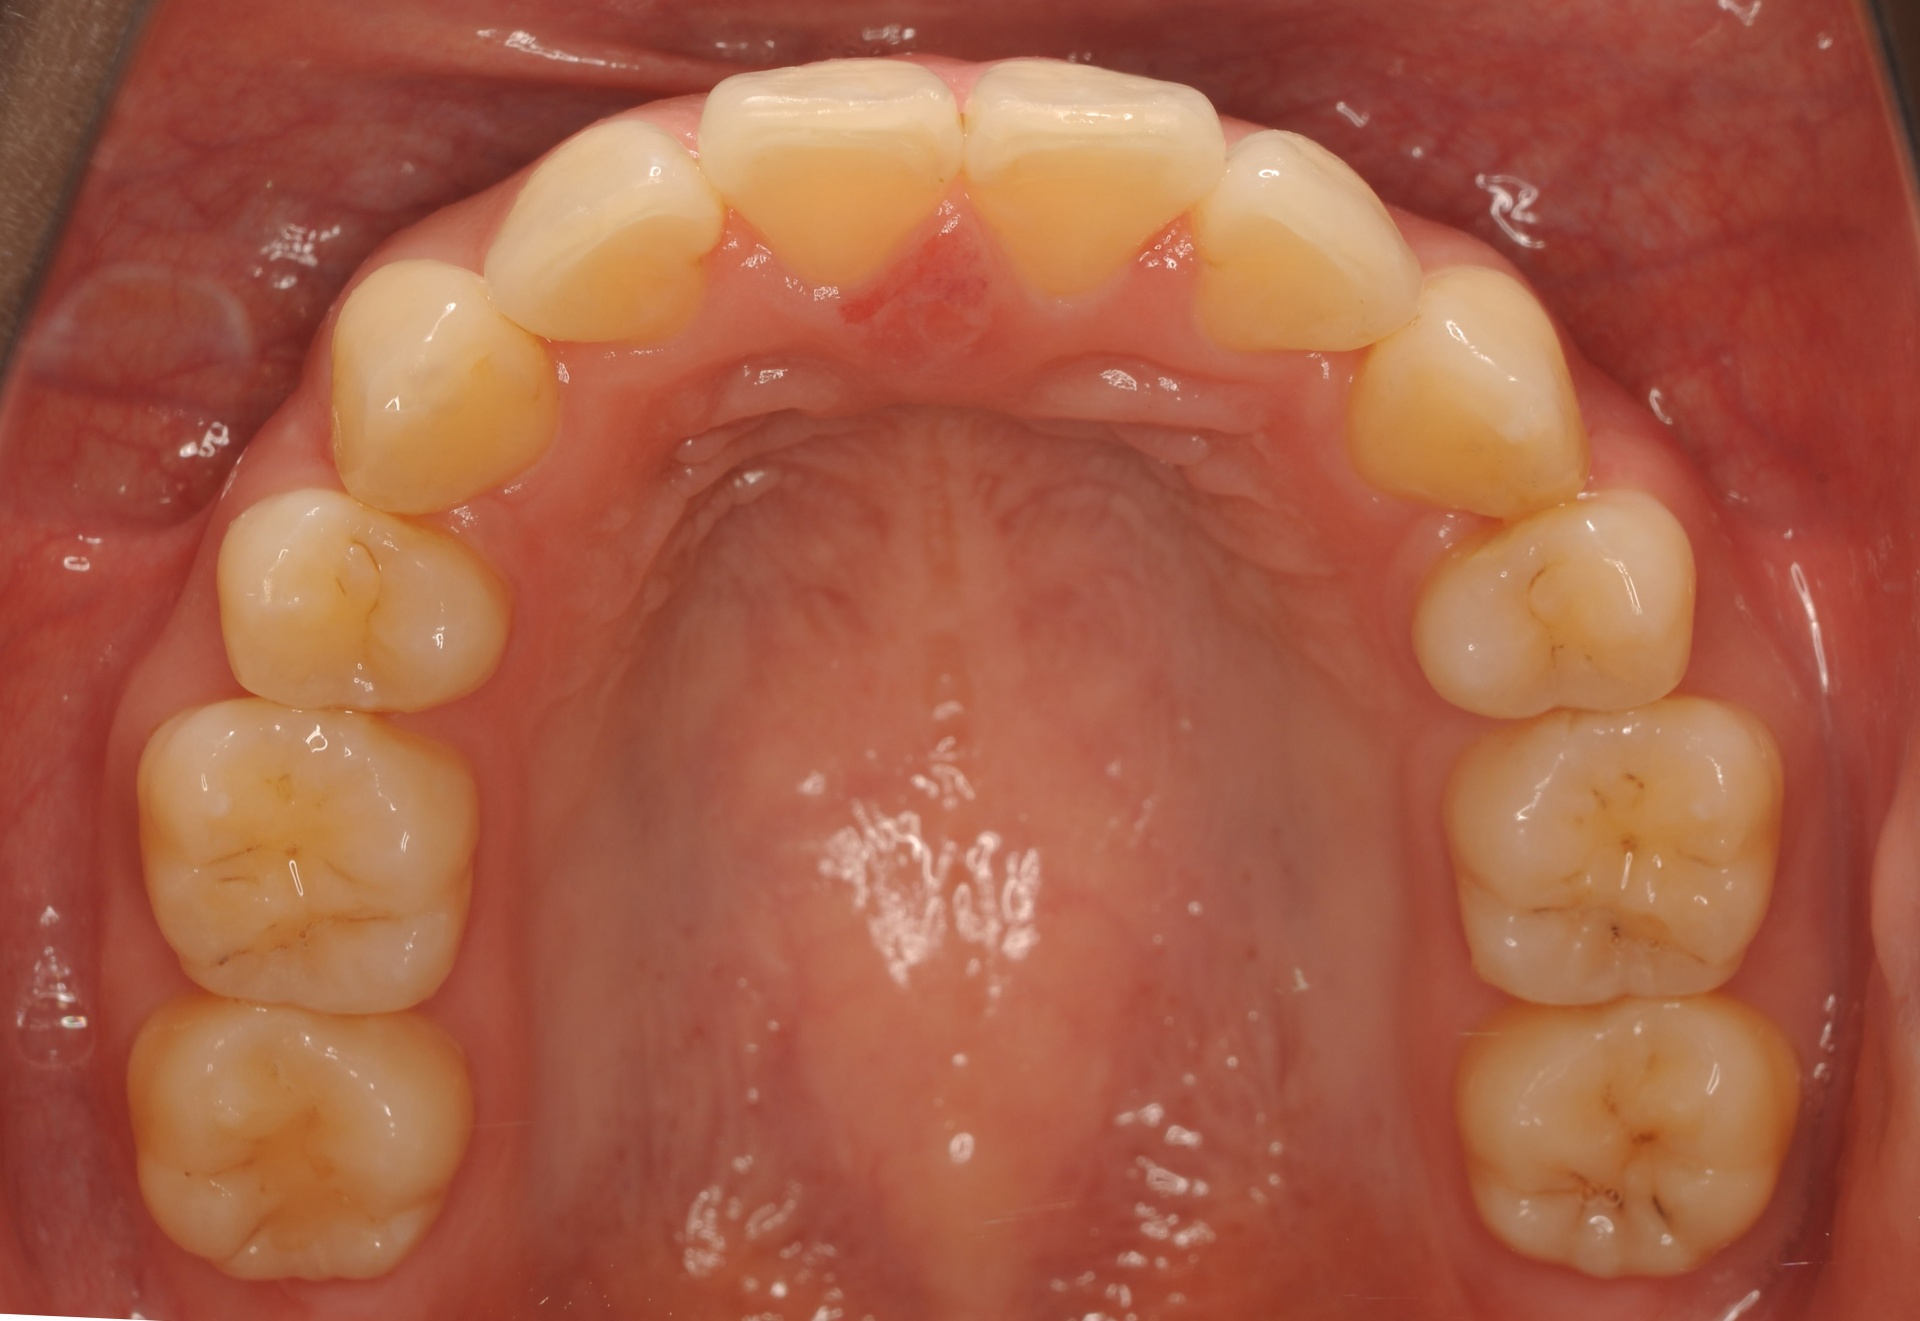

治療後

上下の正中は一致し、上顎両側犬歯は歯列内に誘導されました。奥歯の咬合関係は緊密で、再配列されたことにより機能・審美ともに改善されました。

| 治療内容 | 20代女性 上顎は叢生量が大きいため小臼歯抜歯のスペースを利用し、下顎は非抜歯で叢生を改善し各歯の再配列を行った |